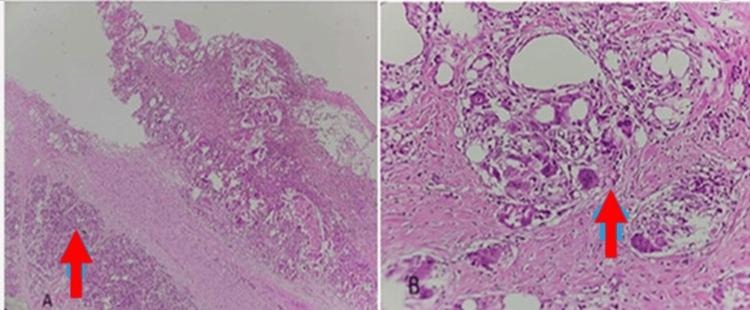

A 56-year-old female presented with left loin pain, intermittent vomiting, and generalized weakness, alongside newly diagnosed diabetes mellitus and hypertension. Initial evaluation revealed a firm, vague mass in the left hypochondrium. Contrast-enhanced magnetic resonance imaging and computed tomography of the kidney, ureter, and bladder showed features consistent with left adrenal myelolipoma, promoting laparoscopic adrenal surgery. During surgery, it was revealed that the mass was adhered to the spleen, tail of the pancreas, and left kidney, and hence laparoscopy was converted to open surgery. In the postoperative period, the patient had a foul-smelling discharge, suggesting a pancreatic duct leak. Therefore, the patient was taken up for emergency splenectomy, distal pancreatectomy, removal of the splenic fissure, and transverse colostomy. Histopathological examination revealed a cystic mass, chronic pancreatitis, and inflammation, with no signs of malignancy. The clinical, investigative, and surgical findings were not indicative of an adrenal mass, emphasizing the need for a team approach and careful assessment while diagnosing retroperitoneal problems.

摘要

一名56岁女性,伴有左腰部疼痛、间歇性呕吐和全身乏力,同时患有新诊断的糖尿病和高血压。初步评估发现左季肋部有一个质地硬、边界不清的肿块。肾脏、输尿管和膀胱的对比增强磁共振成像及计算机断层扫描显示的特征与左肾上腺髓样脂肪瘤相符,遂行腹腔镜肾上腺手术。手术中发现肿块与脾脏、胰尾和左肾粘连,因此将腹腔镜手术转为开放手术。术后患者出现有恶臭的引流物,提示胰管漏。于是,该患者接受了急诊脾切除术、胰体尾切除术、脾裂伤清除术及横结肠造口术。组织病理学检查显示为囊性肿块、慢性胰腺炎和炎症,无恶性迹象。临床、检查及手术结果均不提示肾上腺肿块,强调在诊断腹膜后问题时需要团队协作及仔细评估。